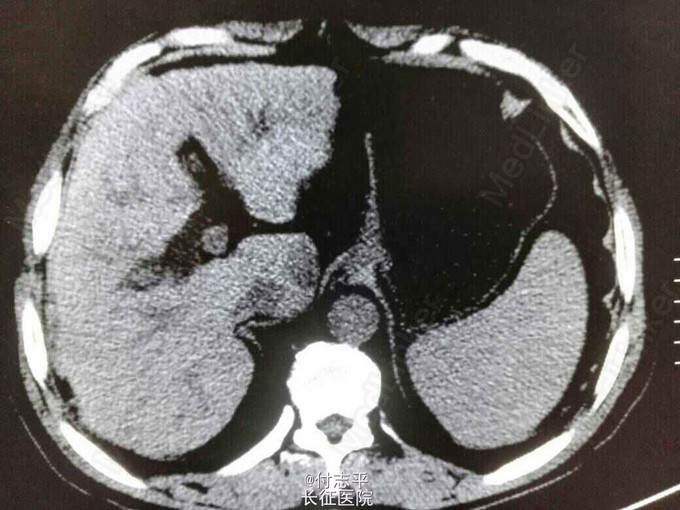

主诉:体检发现AFP升高2月,发现肝占位6天。 病史:患者63岁男性,2个半月前在当地体检发现AFP260.6ng/ml,门诊B超示肝硬化,因无任何伴随症状,未进一步检查。10天前复查 AFP570.3ng/ml,仍未行处理。遂来我院,门诊增强CT示肝尾装叶占位,肝硬化,脾大,脂肪肝,胆囊切除术后。患者一般情况尚可。3年前体检发现“乙肝病毒感染,肝硬化”,抗乙肝病毒治疗“恩替卡韦”至今。40年前因胆结石行胆囊切除术。长期饮酒史,服药后开始戒酒。无家族病史。

诊断:1.原发性肝癌。2.乙肝后肝硬化。3.胆囊切除术后。 治疗:完善术前检查后预备行肝尾状叶占位微波消融术。术中见小肠、大网膜、与原切口瘢痕和肝脏脏面广泛粘连,仔细分离暴露后见肝脏呈轻中度结节性肝硬化表现,质地较硬;于尾状叶实质内探及2cm质硬肿块,边界不清,周围组织及器官未见明显侵犯。由于肿瘤位置较深,超声探头不好摆放,改行肝尾状叶切除术。